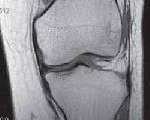

M23.0 Кистозный мениск